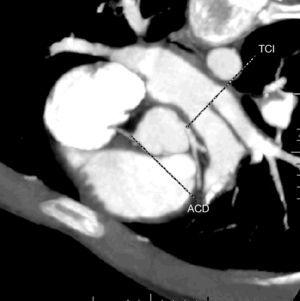

Se muestran las imágenes del árbol coronario que permiten descartar anomalías en esta localización. La figura 1 muestra una proyección axial de máxima intensidad (MIP) de la salida de las arterias coronarias. La figura 2 es una proyección coronal de máxima intensidad (MIP) de la arteria coronaria derecha similar a la proyección oblicua anterior derecha de la angiografía. Las figuras 3 y 4 son reconstrucciones en volume rendering en proyección oblicua anterior izquierda del tronco coronario izquierdo y su bifurcación y de la base del corazón, en la que se visualiza la salida del tronco coronario izquierdo. Se han retirado las venas pulmonares izquierdas. En la estación de trabajo, mediante el análisis avanzado de vasos se puede visualizar un vaso tortuoso o de trayecto curvo en un solo plano tomográfico permitiendo una cuantificación de la lesiones estenóticas. El estudio no detectó anomalía en la anatomía ni estenosis coronaria significativa en el paciente.

Figura 2. Proyección coronal de máxima intensidad de la arteria coronaria derecha similar a la proyección oblicua anterior derecha de la angiografía.